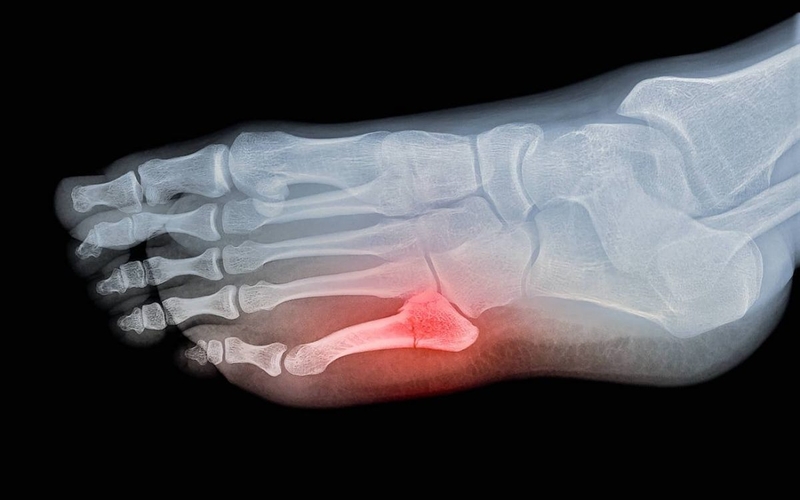

Trong hầu hết các trường hợp, bác sĩ sẽ chẩn đoán gãy xương ngón chân thông qua quá trình thăm khám lâm sàng và chụp X-quang.

Bác sĩ thường có thể phát hiện xương bị di lệch khi quan sát ngón chân của bạn. Tuy nhiên, để đảm bảo sự chính xác, họ vẫn sẽ khuyến nghị chụp X-quang để đánh giá sự tổn thương và xác định được phương pháp điều trị phù hợp cho bệnh nhân.

Gãy ngón chân thường được chụp X-quang để đánh giá mức độ gãy